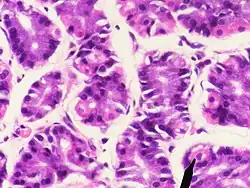

Париета́льная кле́тка (лат. cellula parietalis), также обкла́дочная кле́тка, гландулоци́т париета́льный (лат. glandulocytus parietalis) — клетка желудка, секретирующая соляную кислоту и внутренний фактор Касла.

Париетальные клетки располагаются в наружной части фундальных желёз желудка. Фундальные (синоним главные) железы составляют основную часть желёз области дна, тела и интермедиальной зоны желудка. У мужчин число париетальных клеток — от 0,96 до 1,26 миллиарда, в среднем — 1,09 миллиарда; у женщин — от 0,69 до 0,91 миллиарда, в среднем — 0,82 миллиарда. Один миллиард париетальных клеток за один час секретирует в среднем 23 ммоль соляной кислоты. Максимальные объём секреции в час соляной кислоты у мужчин 22—29 ммоль, у женщин — 16—21 ммоль.[1]